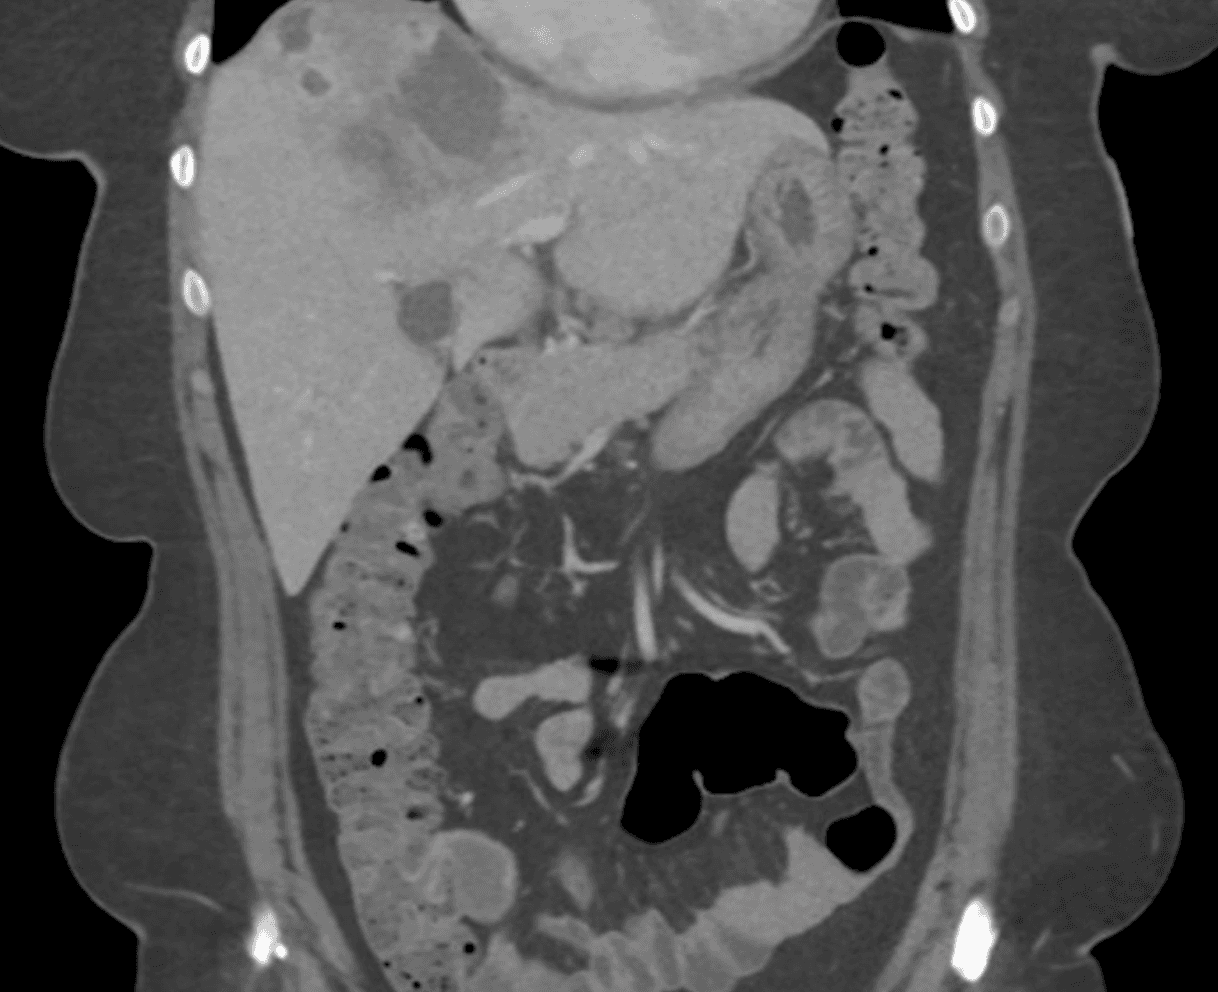

Complete blood count shows white blood cell count 14,200/μL with 32% eosinophils (absolute eosinophil count 4,540/μL), hemoglobin 12.4 g/dL, and platelets 310,000/μL. Comprehensive metabolic panel shows ALT 178 U/L, AST 142 U/L, alkaline phosphatase 312 U/L, and total bilirubin 1.1 mg/dL. Three stool ova and parasite examinations performed on consecutive days return negative. Hepatitis A, B, and C serologies are negative. A contrast-enhanced CT of the abdomen is obtained.

CT abdomen with contrast, coronal view. Hepatomegaly with multiple hypodense nodular lesions and linear migratory tracts in the right hepatic lobe.